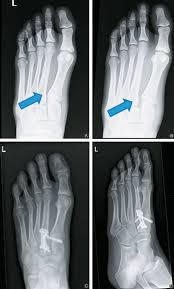

It is possible to sprain the lisfranc ligament, which does not require surgical intervention. A lisfranc injury, also known as a lisfranc fracture, happens when bones break or ligaments tear in the region in the middle of the feet. Sometimes, the injury is a simple dislocation (ligament injury), and sometimes a broken bone occurs. Partial ligament tears with no instability normal lisfranc. A lisfranc injury or lisfranc sprain is an injury to the ligaments in the middle part of the foot, called the midfoot.

Lisfranc injuries are a spectrum of injuries to the tarsometatarsal joint complex of the midfoot. Lisfranc was a napoleanic general in the cavalry. The injury is named after jacques lisfranc de st. An untreated lisfranc injury can lead to serious complications. A lisfranc injury, also known as a lisfranc fracture, happens when bones break or ligaments tear in the region in the middle of the feet. Lisfranc injury is an important topic. Admin , dieter schuddinck , adam west , jan de backer , kim jackson , rachael lowe , lynn leemans , celine de wolf , simisola ajeyalemi , adam vallely farrell , amanda ager , wikisysop , leana louw and wanda van niekerk. Learn vocabulary, terms and more with flashcards, games and other moi for lisfranc injuries?

Radiologists must have a thorough understanding of anatomy, mechanisms, and patterns of these injuries to diagnose and help. A lisfranc injury, also known as a lisfranc fracture, happens when bones break or ligaments tear in the region in the middle of the feet. A lisfranc injury occurs when one or more of the metatarsal bones are displaced from the tarsus, which is a cluster of bones at the top of the foot, just below the ankle joint. However, most athletes are able to successfully. Stable lisfranc injuries that do not require surgery may cause an athlete to miss 2 months or more of their season. Lisfranc injuries are a spectrum of injuries to the tarsometatarsal joint complex of the midfoot. Lisfranc injury or midfoot injury that result if bones in the midfoot are broken or ligaments that support the midfoot are torn. • medial edge of 2nd mt base should line up with the medial edge of middle cuneiform. A lisfranc injury or lisfranc sprain is an injury to the ligaments in the middle part of the foot, called the midfoot. Lisfranc injury indicates disruption between. Recovery can be slow and painful. It can occur in one or both feet. Ebraheim's animated educational video describing lisfranc injury.